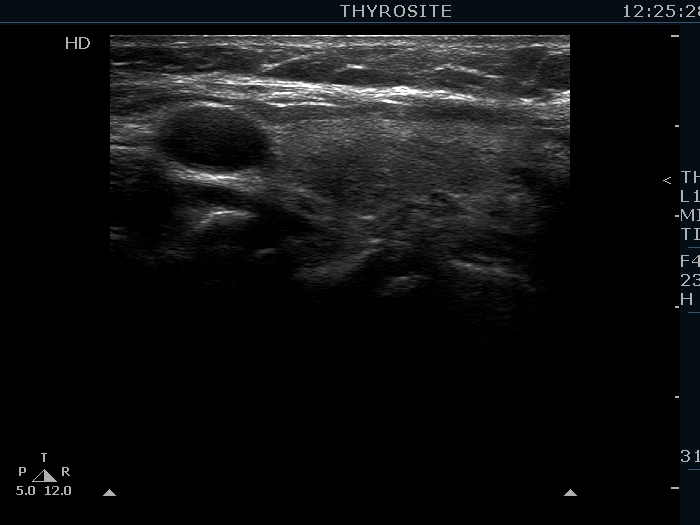

Intranodular hyperechogenic figures - case 876 (ultrasonographic picture 6)

Left lobe, longitudinal scan.